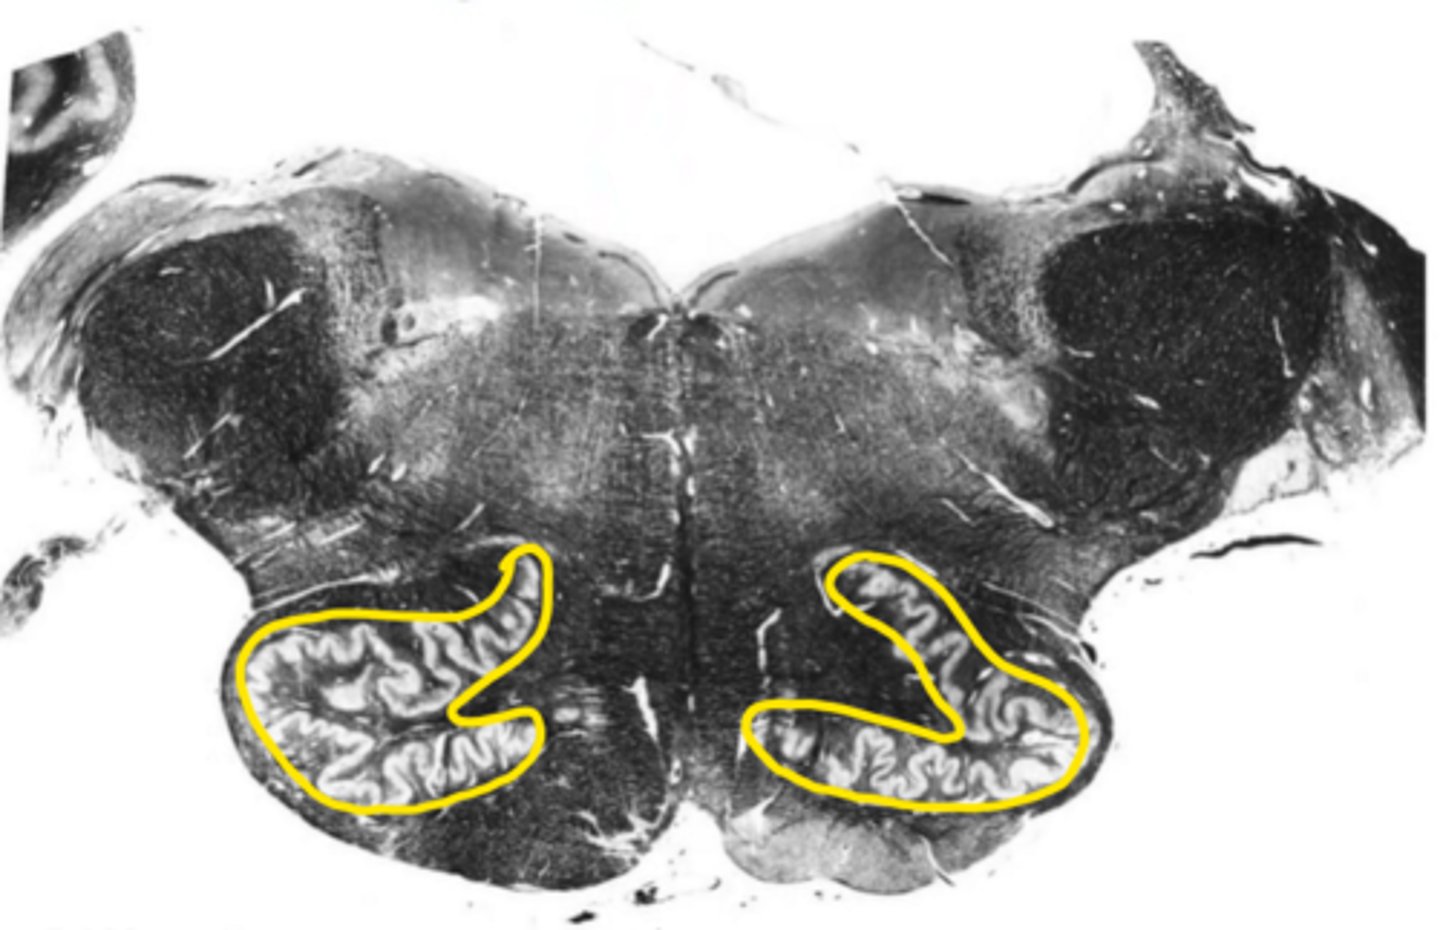

principle olivary nucleus

ID the structure

closed medulla

ID the brainstem level